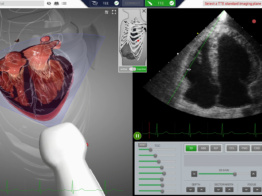

HeartWorks

A globally recognized cardiac learning platform, with simulation in cardiac anatomy, transthoracic, transesophageal echocardiography (TTE/TEE) and live 3D echocardiography. Ideal for programs prioritizing realistic cardiac anatomy and pathology.

TTE, TEE & Live 3D Echo